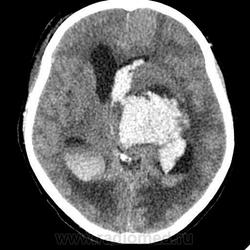

КТ головного мозга, кровоизлияние.

"Скорая" привезла женщину 75 лет, найденную на улице. На КТ направлена с д-зом: кома неясного происхождения. Вот такая картина на КТ.

Острое внутримозговое кровоизлияние с выходом крови в желудочки (боковые - сгустки преимущественно в левом + эффект седиментации с горизонтальным уровнем жидкость\жидкость в задних рогах; сгустки крови в третьем желудочке, кровь в четвертом). Значительное увеличение височных рогов боковых желудочков - гидроцефалия. Смешение срединных структур вправо, отек белого вещества перивентрикулярно слева.

Довольно большие кровоизлияния в стволе мозга (что объясняет тяжесть состояния).

Остается вопрос по слегка гиперденсному (относительно серго вещества) однородному фокусу в левой лобной доле... и по причине кровоизлияния. Что касается последнего могу предположить патологию базилярной артерии (разрыв аневризмы?)... правда не вижу что-то крови в цистернах основания черепа.

Я написала отек мозга, острое массивное (около 100 мл только внутримозговое) смешанное кровоизлияние слева + в стволе, с прорывом и гемотампонадой желудочков, выраженной латеральной дислокацией (13 мм), менингиома? лобного полюса слева. Убедительных данных за опухоль, давшую кровоизлияние, не вижу, хотя такая мысль тоже была.  Контрастировать такую пациентку никто не будет, агонизирующая(.

У, сколько всего написано. Пока не пришла Nela, поучаствую и я. 1. Кровоизлияние в ткань мозга, а не в опухоль: а)не видно ткани опухоли; б) неясна первичная локализация опухоли (левые базальные ядра?!); в)нет перифокального отека вокруг предролагаемой опухоли, г) при опухолях прорывы в желудочки - редкость; 2) к поперечной дислокации добавил бы безесловную аксиальную: даже цистерна моста сужена, не говоря уже про обходную-четверохолмную и другие; 3) менингиома в левой лобной области, на мой взгляд, сомнительна (кстати, покажите ее пожалуйста), ИМХО - "игра" плотностей;  4) ///метастазы в сосудистые сплетения/// - это очень круто, но они не дали бы внутримозгового кровоизлияния, как и ///плексуспапилома///.

Массивное медиальное кровоизлияние с прорывом в желудочки. Кровоизлияние в ствол. Признаки вклинения. В лбу может что-то и есть, но это не принципиально. А может быть и отечные извилины. Смущает, что нет масс-эффекта.

Причина таких кровоизлияний, как правило, гипертензия и атеросклероз.

Кровоизлияние не связанное с объемным образованием, "гипертоническое", основной массой - в области базальных ядер, кровоизлияние в ствол мозга, кома ясного происхождения :) А менингиома менигниомой, не мешает, так сказать.  Отека мозга здесь небольшой, больше выражено набухание.